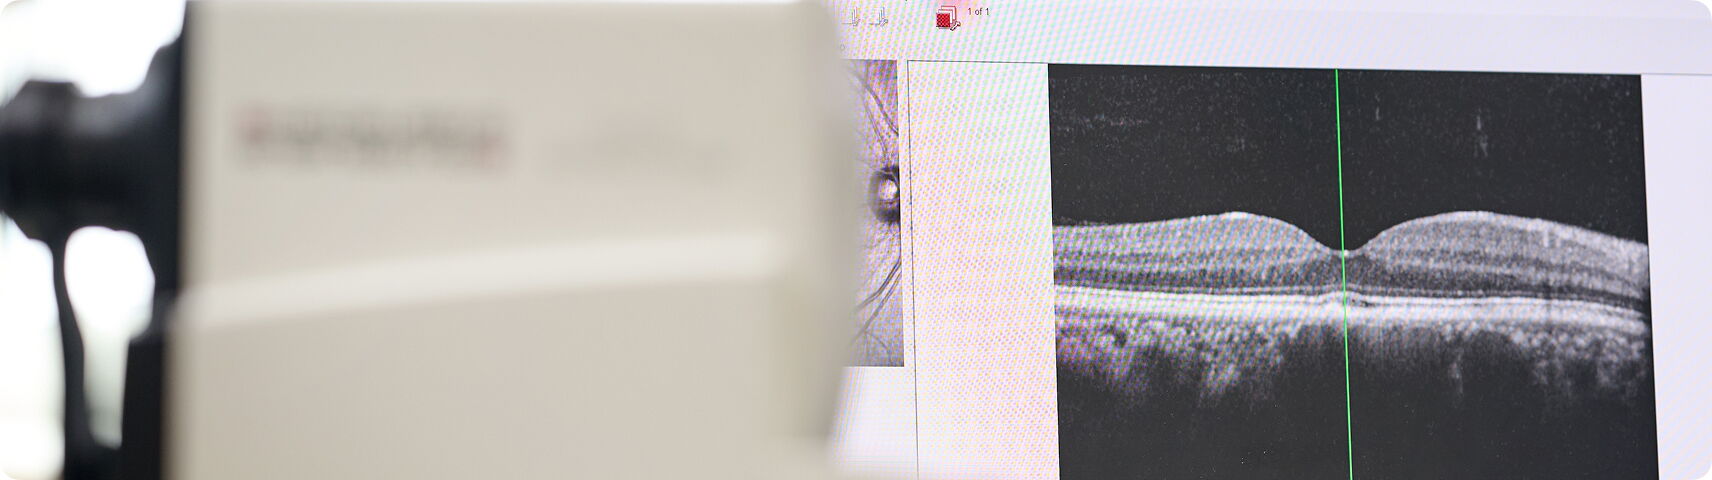

Veränderungen an der Netzhaut können das Sehvermögen stark beeinflussen. Wir diagnostizieren und behandeln Netzhauterkrankungen frühzeitig und gezielt.

Eine Makuladegeneration ist eine Netzhauterkrankung, bei der es mit zunehmendem Alter zu Schädigungen der Stelle des schärfsten Sehens (der Makula) kommt.

Bei der feuchten Form wachsen zusätzlich neue Blutgefäße unter die Stelle des schärfsten Sehens. Diese neu gebildeten Blutgefäße haben undichte Gefäßwände und es kommt zu einer Flüssigkeitsanreicherung unter oder innerhalb der Netzhaut (feuchte Makula). Dies führt zu einer erheblichen Sehverschlechterung innerhalb kurzer Zeit. Es gibt eine wirksame Behandlung für diese Form, jedoch ist eine rechtzeitige Behandlung zum Erhalt des Sehens wichtig.